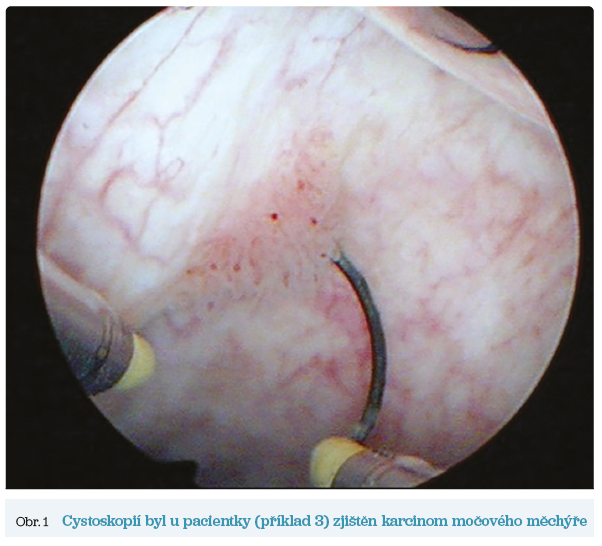

Obr. 1 Cystoskopií byl u pacientky (příklad 3) zjištěn karcinom močového měchýřePreskripce byla opakována bez kontrol. Občasné nekomplikované cystitidy řešeny podáním che­mo­te­ra­peu­tik v řádném dávkování. V posledním půlroce před odborným vyšetřením si stěžuje na hematurii.

Provedenou cystoskopií zjištěn karcinom močového měchýře s následnou terapií (obr. 1).